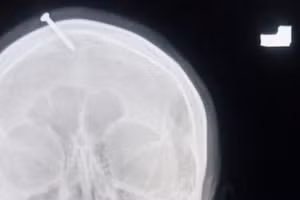

GD&TĐ - Các bác sĩ tại Bệnh viện Lady Reading ở Peshawar đã vô cùng sửng sốt khi kiểm tra đầu của một phụ nữ mang thai, khi cô ấy khẳng định có một chiếc đinh cắm trong hộp sọ của mình.